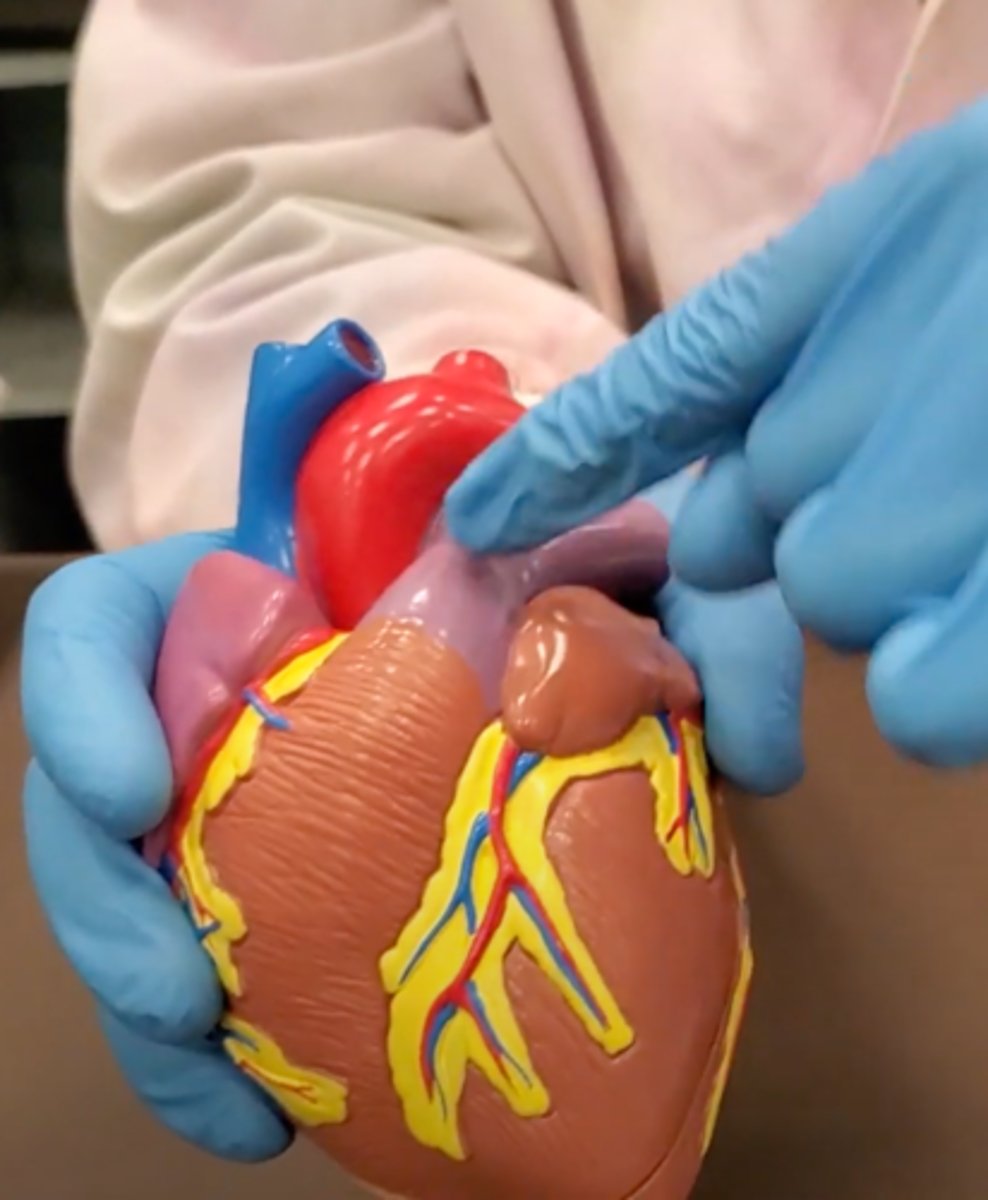

pulmonary trunk (model)

yellow sash of fat that tells you this if the front side of the heart (model)

t-shaped ribbon of fat on back side of heart (model)

Left ventricle (model)

has the most muscle mass because it has to pump blood to the whole body

apex (model)

base (model)

where everything connects